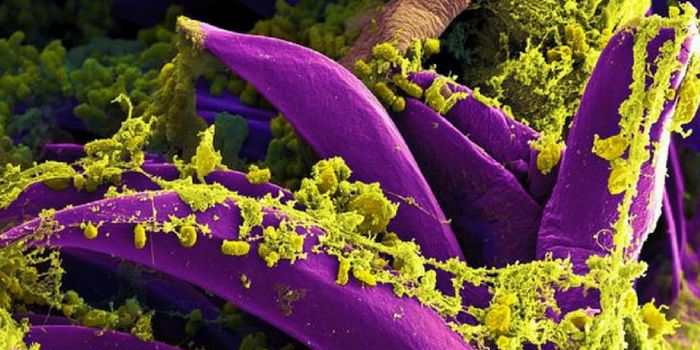

OCT 27, 2017Clinical & Molecular DXMadagascar is currently battling a plague outbreak that has so far infected nearly 1,200 people and killed 124 people. I ...